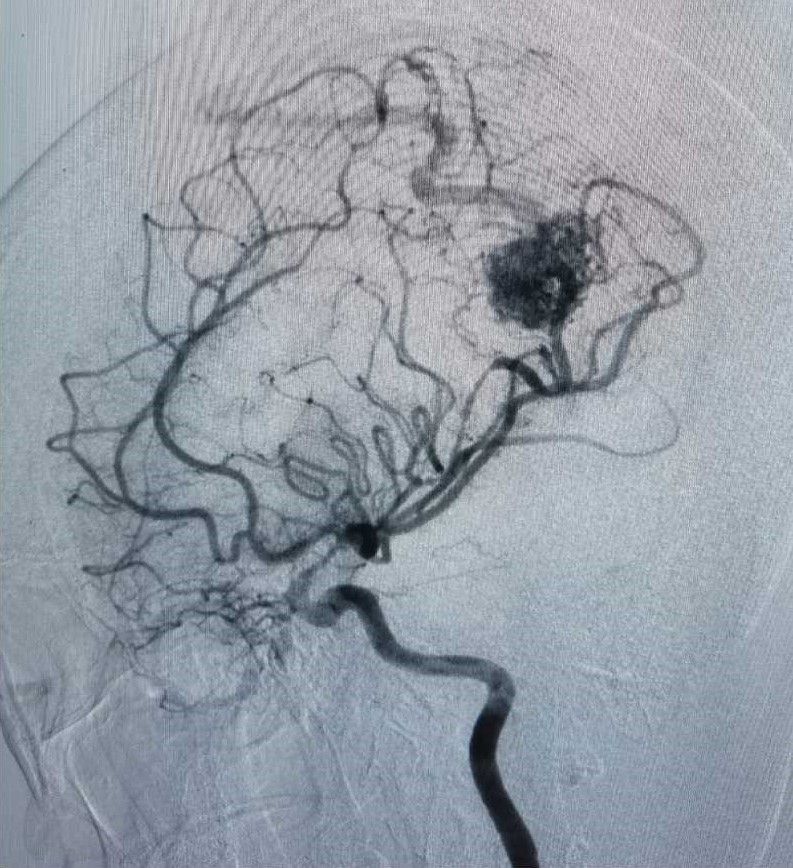

行DSA检查

显示畸形血管团为20*23mm,多支动脉参与供血,引流至上矢状窦。